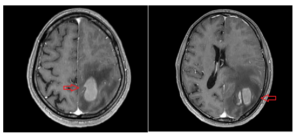

Ca lâm sàng: Hiệu quả điều trị phối hợp: Miễn dịch-Hóa chất và Xạ phẫu dao gamma quay bệnh nhân ung thư phổi di căn não tại Trung tâm Y học hạt nhân và Ung bướu, Bệnh viện Bạch Mai

Ca lâm sàng: Hiệu quả điều trị phối hợp: Miễn dịch-Hóa chất và Xạ phẫu dao gamma quay bệnh nhân ung thư phổi di căn não tại Trung tâm Y học hạt nhân và Ung bướu, Bệnh viện Bạch Mai GS.TS Mai Trọng Khoa1,2, PGS. TS Phạm Cẩm Phương1,2,...